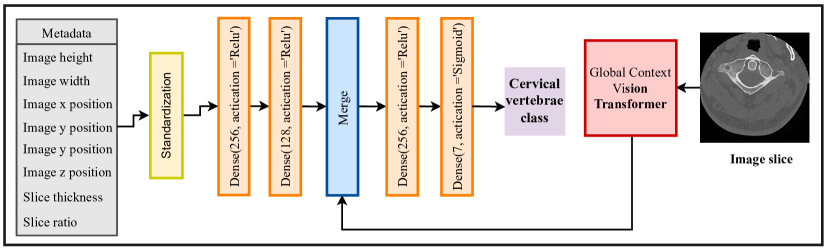

This section outlines the methodology employed for cervical vertebrae classification in the current study. To achieve this objective, a multi-input deep neural network is leveraged for vertebrae classification. This network accommodates two types of inputs: images and metadata, both of which contain essential features such as image positions and slice ratios. Given the sequential nature of image acquisition in CT imaging, the inclusion of these metadata features proves particularly advantageous. The network architecture integrates the Global Context Vision Transformer, with pre-trained weights, to handle the image input, while the metadata input undergoes processing through three fully connected layers. Subsequently, the extracted features from both inputs are concatenated, and two additional fully connected layers are employed for the final classification. The schematic of the network is presented in Figure 5

Furthermore, a learning rate reduction strategy is implemented through the utilization of the callback. This strategy continuously monitors the validation macro F1 score and dynamically adjusts the learning rate during the training process. This adaptive learning rate strategy serves the dual purpose of enhancing model convergence and improving overall performance.

In order to assess the effectiveness of the approach employed, several deep learning models, including ResNet152V2, VGG19, DenseNet, ConvNext, Vision Transformer, and Swin Transformer, are implemented. These models operate solely on image inputs for the classification of vertebrae. The outcomes of these model implementations are summarized in Table 1.